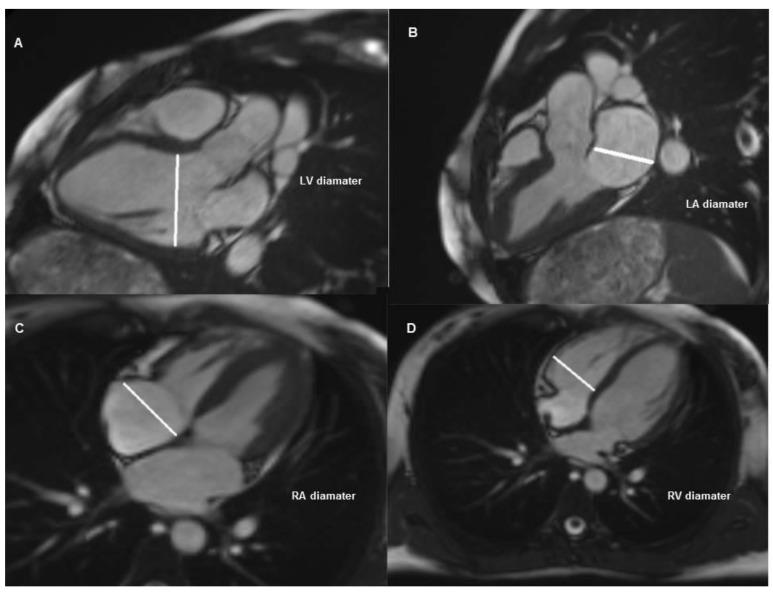

Cardiac magnetic resonance (CMR) imaging is the gold standard method for the detection of ventricular volumes and myocardial edema/scar. Transthoracic echocardiography (TTE) imaging is primarily used in the evaluation of cardiac functions and chamber dimensions. This study aims to investigate whether the chamber diameter measurements are concordant with each other in the same patient group who underwent TTE and CMR. The study included 41 patients who underwent TTE and CMR imaging. Ventricular and atrial diameter measurements from TTE-derived standard parasternal long axis and apical four-chamber views and CMR-derived three- and four-chamber views were recorded. The concordance between the two methods was compared using intra-class correlation coefficients (ICC) and Bland-Altman plots. Of the patients, 25 (61%) were male and the mean age was 48.12 ± 16.79. The mean ICC for LVDD between CMR observers was 0.957 (95% CI: 0.918-0.978), while the mean ICC between CMR and TTE measurements were 0.849 (95% CI: 0.709-0.922) and 0.836 (95% CI: 0.684-0.915), respectively. The mean ICC for the right ventricle between CMR observers was 0.985 (95% CI: 0.971-0.992), while the mean ICC between CMR and TTE measurements were 0.869 (95% CI: 0.755-0.930) and 0.892 (95% CI: 0.799-0.942), respectively. Passing-Bablok Regression and Bland-Altman plots indicated high concordance between the two methods. TTE and CMR indicated high concordance in chamber diameter measurements for which the CMR should be considered in patients for whom optimal evaluation with TTE could not be performed due to their limitations.

心脏磁共振(CMR)成像被认为是检测心室容积和心肌水肿/瘢痕的金标准方法。经胸超声心动图(TTE)成像主要用于评估心脏功能和心室尺寸。本研究旨在探讨 TTE 和 CMR 检查的同一患者组的腔径测量值是否相互一致。该研究纳入了 41 例行 TTE 和 CMR 成像的患者。记录 TTE 衍生的标准胸骨旁长轴和心尖四腔视图以及 CMR 衍生的三腔和四腔视图的心室和心房直径测量值。使用组内相关系数(ICC)和 Bland-Altman 图比较两种方法的一致性。患者中,25 例(61%)为男性,平均年龄为 48.12±16.79 岁。CMR 观察者之间的 LVDD 平均 ICC 为 0.957(95%CI:0.918-0.978),而 CMR 和 TTE 测量值之间的平均 ICC 分别为 0.849(95%CI:0.709-0.922)和 0.836(95%CI:0.684-0.915)。CMR 观察者之间右心室的平均 ICC 为 0.985(95%CI:0.971-0.992),而 CMR 和 TTE 测量值之间的平均 ICC 分别为 0.869(95%CI:0.755-0.930)和 0.892(95%CI:0.799-0.942)。Passing-Bablok 回归和 Bland-Altman 图表明两种方法具有高度一致性。TTE 和 CMR 在腔径测量方面具有高度一致性,对于因 TTE 局限性而无法进行最佳评估的患者,应考虑使用 CMR。